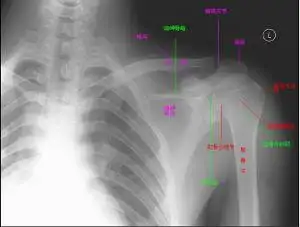

肩部骨架图片

正常距离为10~15mm,狭窄为小于10mm,严重肩袖损伤为小于5mm.